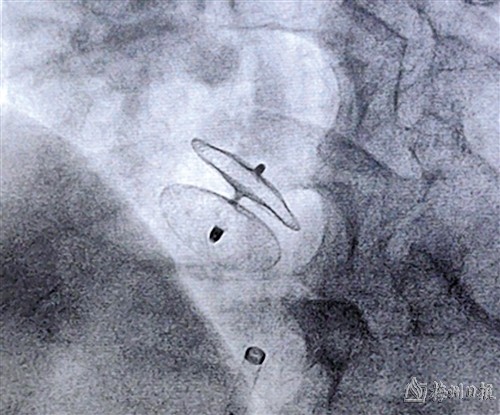

术中成功释放封堵器

卵圆孔未闭介入封堵治疗通过微创手术在患者局麻下完成,将封堵器封堵于未闭卵圆孔。封堵后通过经胸壁超声心动图判断封堵器位置及是否影响心脏瓣膜功能,通过经颅多普勒超声发泡试验及经胸壁超声心动图右心声学造影观察残余分流情况。